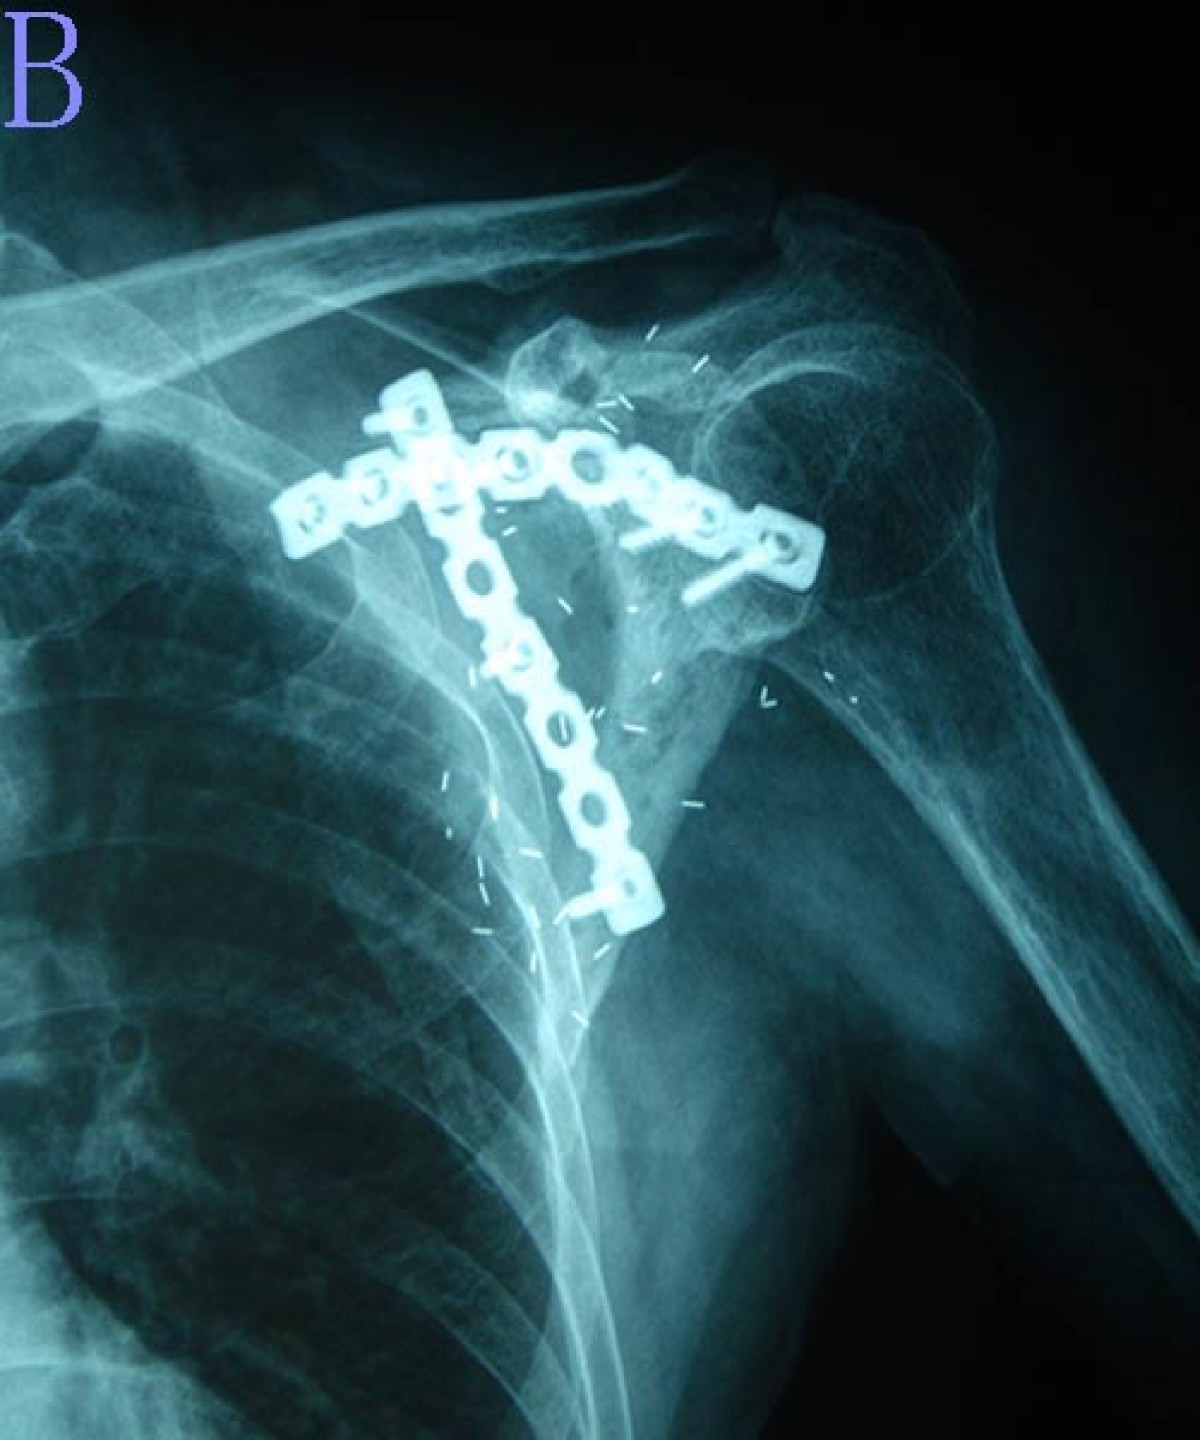

From www.researchgate.net

(a), Xray images show right scapula and that distal clavicle is Scapula Bone Cancer a wide variety of benign and malignant tumors may occur in the scapula with mostly cartilaginous and metastatic tumors, and. Risk for malignancy increased with age (or 1.09,. chondrosarcoma is a malignant mesenchymal tumor originating from cartilage. tumors occurred most frequently in the body of the scapula. previous studies have shown that primary bone tumours of. Scapula Bone Cancer.